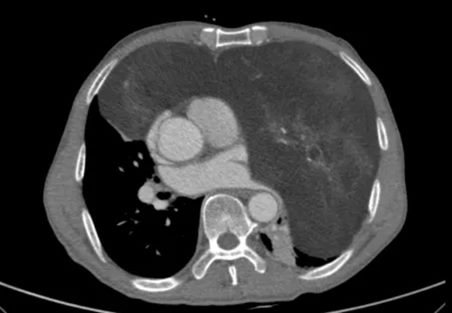

怀着忐忑的心情,家人陪同老人来到郑州大学第五附属医院胸外科就诊。完善胸部增强CT检查后,结果让经验丰富的高兴才主任也为之震惊:患者的前纵隔、左侧胸腔乃至部分右侧胸腔,被一个巨大的混杂密度团块所占据,其长径达23cm!这个巨大的瘤体几乎占满左侧胸腔,严重挤压纵隔使其向右移位,左肺因受压而萎陷。这正是导致老人长期胸闷、呼吸不畅的“罪魁祸首”。